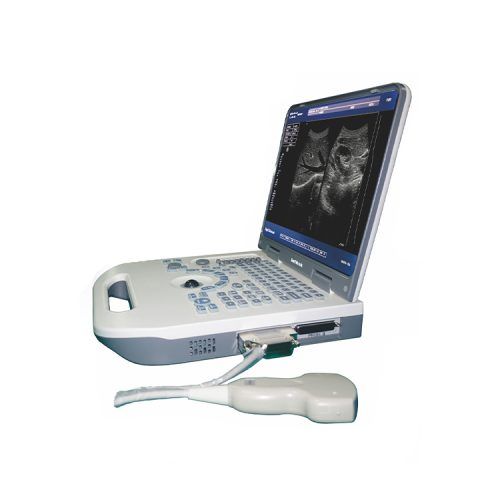

超声仪, 多普勒, US-HCE20

1. 12英寸液晶显示屏

2. Windows 7平台操作系统

3. THI成像技术

1. 高分辨率12英寸LED,具有倾斜功能

2.用户友好的键盘和控件

1. THI增强对比度分辨率

2. IP快速图像优化

1.配备固态硬盘,使存储更安全可靠,

| 型号 | 美国-HCE20 |

| 显示 | 12寸液晶屏 |

| 操作系统 | Windows 7的 |

| 电池 | 3200毫安时 |

| 显示模式 | B、 B/B、4B、B+M、CFM、B+CFM、PDI、B+PDI、PW |

| 灰度 | 256 个级别 |

| 图像优化 | 5个级别 |

| 支持语言 | CN、EN、RUS、POR、ESP、FR、DE |

| 显示穿透深度 | 1~400mm |

| 动态范围 | 80~280分贝 |

| 应用方式 | 妇产科、小器官、泌尿科、儿科、心脏等 |

| 伪彩 | 15种 |

| 硬盘 | 120G |

| 频率范围 | 2MHz~12MHz |

| 增益控制 | 8段 |

| 焦点位置 | 动态电子聚焦 |

| 界面 | HDMI、VGA、DICOM、USB、线路输出。 |